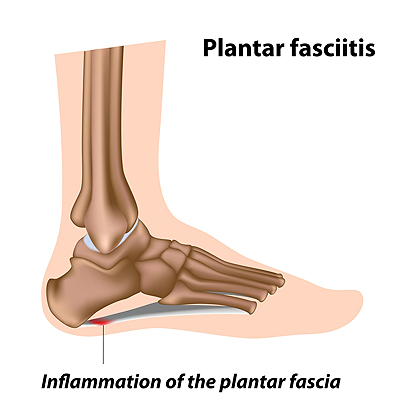

Heel and Arch Pain May Indicate Plantar Fasciitis

Plantar fasciitis is a common foot condition that many patients suffer from. It occurs when the plantar fascia becomes inflamed and can cause severe difficulty in walking. The plantar fascia is a band of tissue that connects the heel to the toes, and is found along the sole of the foot. Plantar fasciitis can be caused for a variety of reasons, including standing on hard surfaces for the majority of the day, wearing shoes that do not fit correctly, or it may come from having low or high arches. The pain is often felt in the heel and may be worse upon arising in the morning. It can help to perform specific stretches, and mild relief may be found when supportive insoles are worn. In severe cases, splints may have to be worn while sleeping, and this may help to stretch the feet. If you have heel pain, it is strongly suggested that you seek the counsel of a podiatrist who can effectively treat plantar fasciitis.

Plantar fasciitis is a common foot condition that many patients suffer from. It occurs when the plantar fascia becomes inflamed and can cause severe difficulty in walking. The plantar fascia is a band of tissue that connects the heel to the toes, and is found along the sole of the foot. Plantar fasciitis can be caused for a variety of reasons, including standing on hard surfaces for the majority of the day, wearing shoes that do not fit correctly, or it may come from having low or high arches. The pain is often felt in the heel and may be worse upon arising in the morning. It can help to perform specific stretches, and mild relief may be found when supportive insoles are worn. In severe cases, splints may have to be worn while sleeping, and this may help to stretch the feet. If you have heel pain, it is strongly suggested that you seek the counsel of a podiatrist who can effectively treat plantar fasciitis.

What Is Plantar Fasciitis?

Plantar fasciitis is the inflammation of the thick band of tissue that runs along the bottom of your foot, known as the plantar fascia, and causes mild to severe heel pain.

What Causes Plantar Fasciitis?

Plantar fasciitis is one of the most common causes of heel pain. The plantar fascia is the thick band of tissue that connects the heel bone to the toes. When this band of connective tissue becomes inflamed, plantar fasciitis occurs. Fortunately, this condition is treatable.